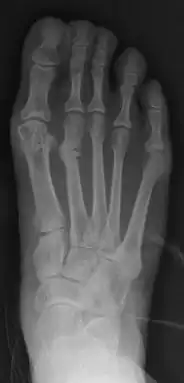

![]() | |

| Stress fracture of the second metatarsal bone (below the knuckles of the second toe) | |